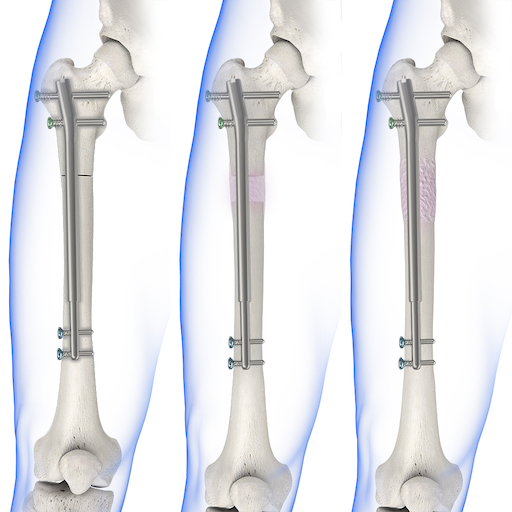

2. Getting hair transplant

9. Limb lengthening surgery

9. Limb lengthening surgery